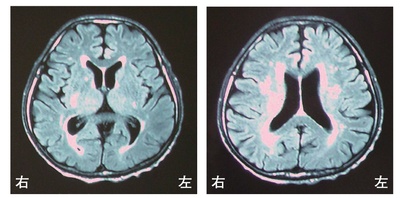

脳梗塞の発生部位によって出現する症状は異なります。この問題では、それぞれの部位における症状を正確に理解することが求められています。

右内包後脚では、左上下肢の運動麻痺が見られるため、この選択肢は正しいです。